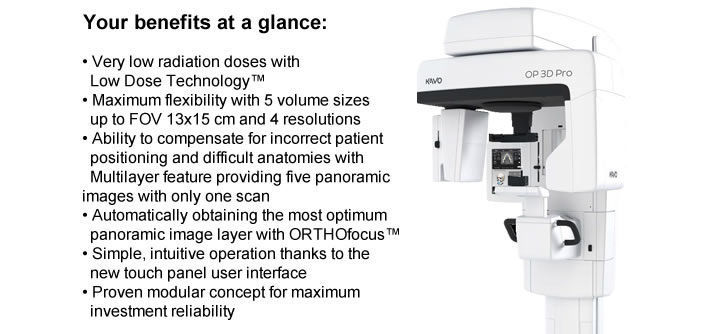

Kako bi vam pružili kvalitetan i detaljan pregled koristimo rengen uređaj KAVO OP 3D Pro s kojim možemo napraviti 2D rengensku snimku čeljusti (Ortopan) ili 3D snimku (CBCT čeljusti).

Uređaj koji mi koristimo ima mogućnosti snimanja u 4 rezolucije. Tako se količina zračenja može kontrolirati i smanjiti ovisno o indikaciji koju postavi Vaš doktor.